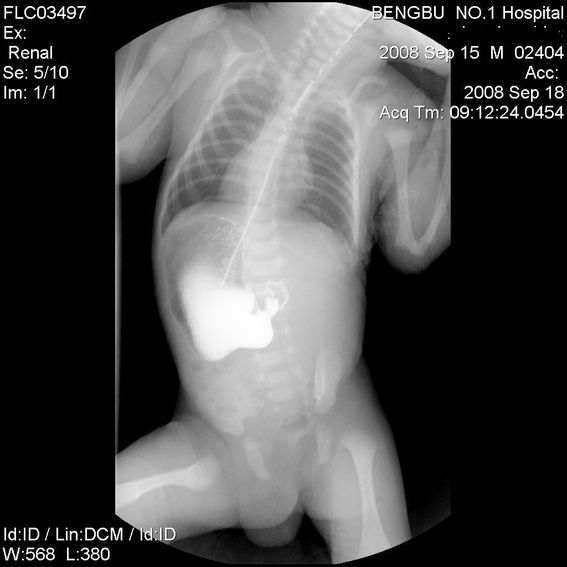

标题: PED1734:男,3天,以呕吐来诊。

十二指肠降部钡流不能顺利通过,胃及十二指肠球扩张。

考虑----十二指肠降部狭窄-----〔但这几个片子狭窄未能清楚显示,无法判断分型-----膜性或管状〕

考虑----十二指肠降部狭窄

十二指肠降部狭窄(可能为环状胰腺)。

十二指肠降部钡流不能顺利通过,胃及十二指肠球扩张,符合十二指肠降部狭窄

符合十二指肠降部狭窄或扭转不良.

考虑十二指肠降部狭窄.